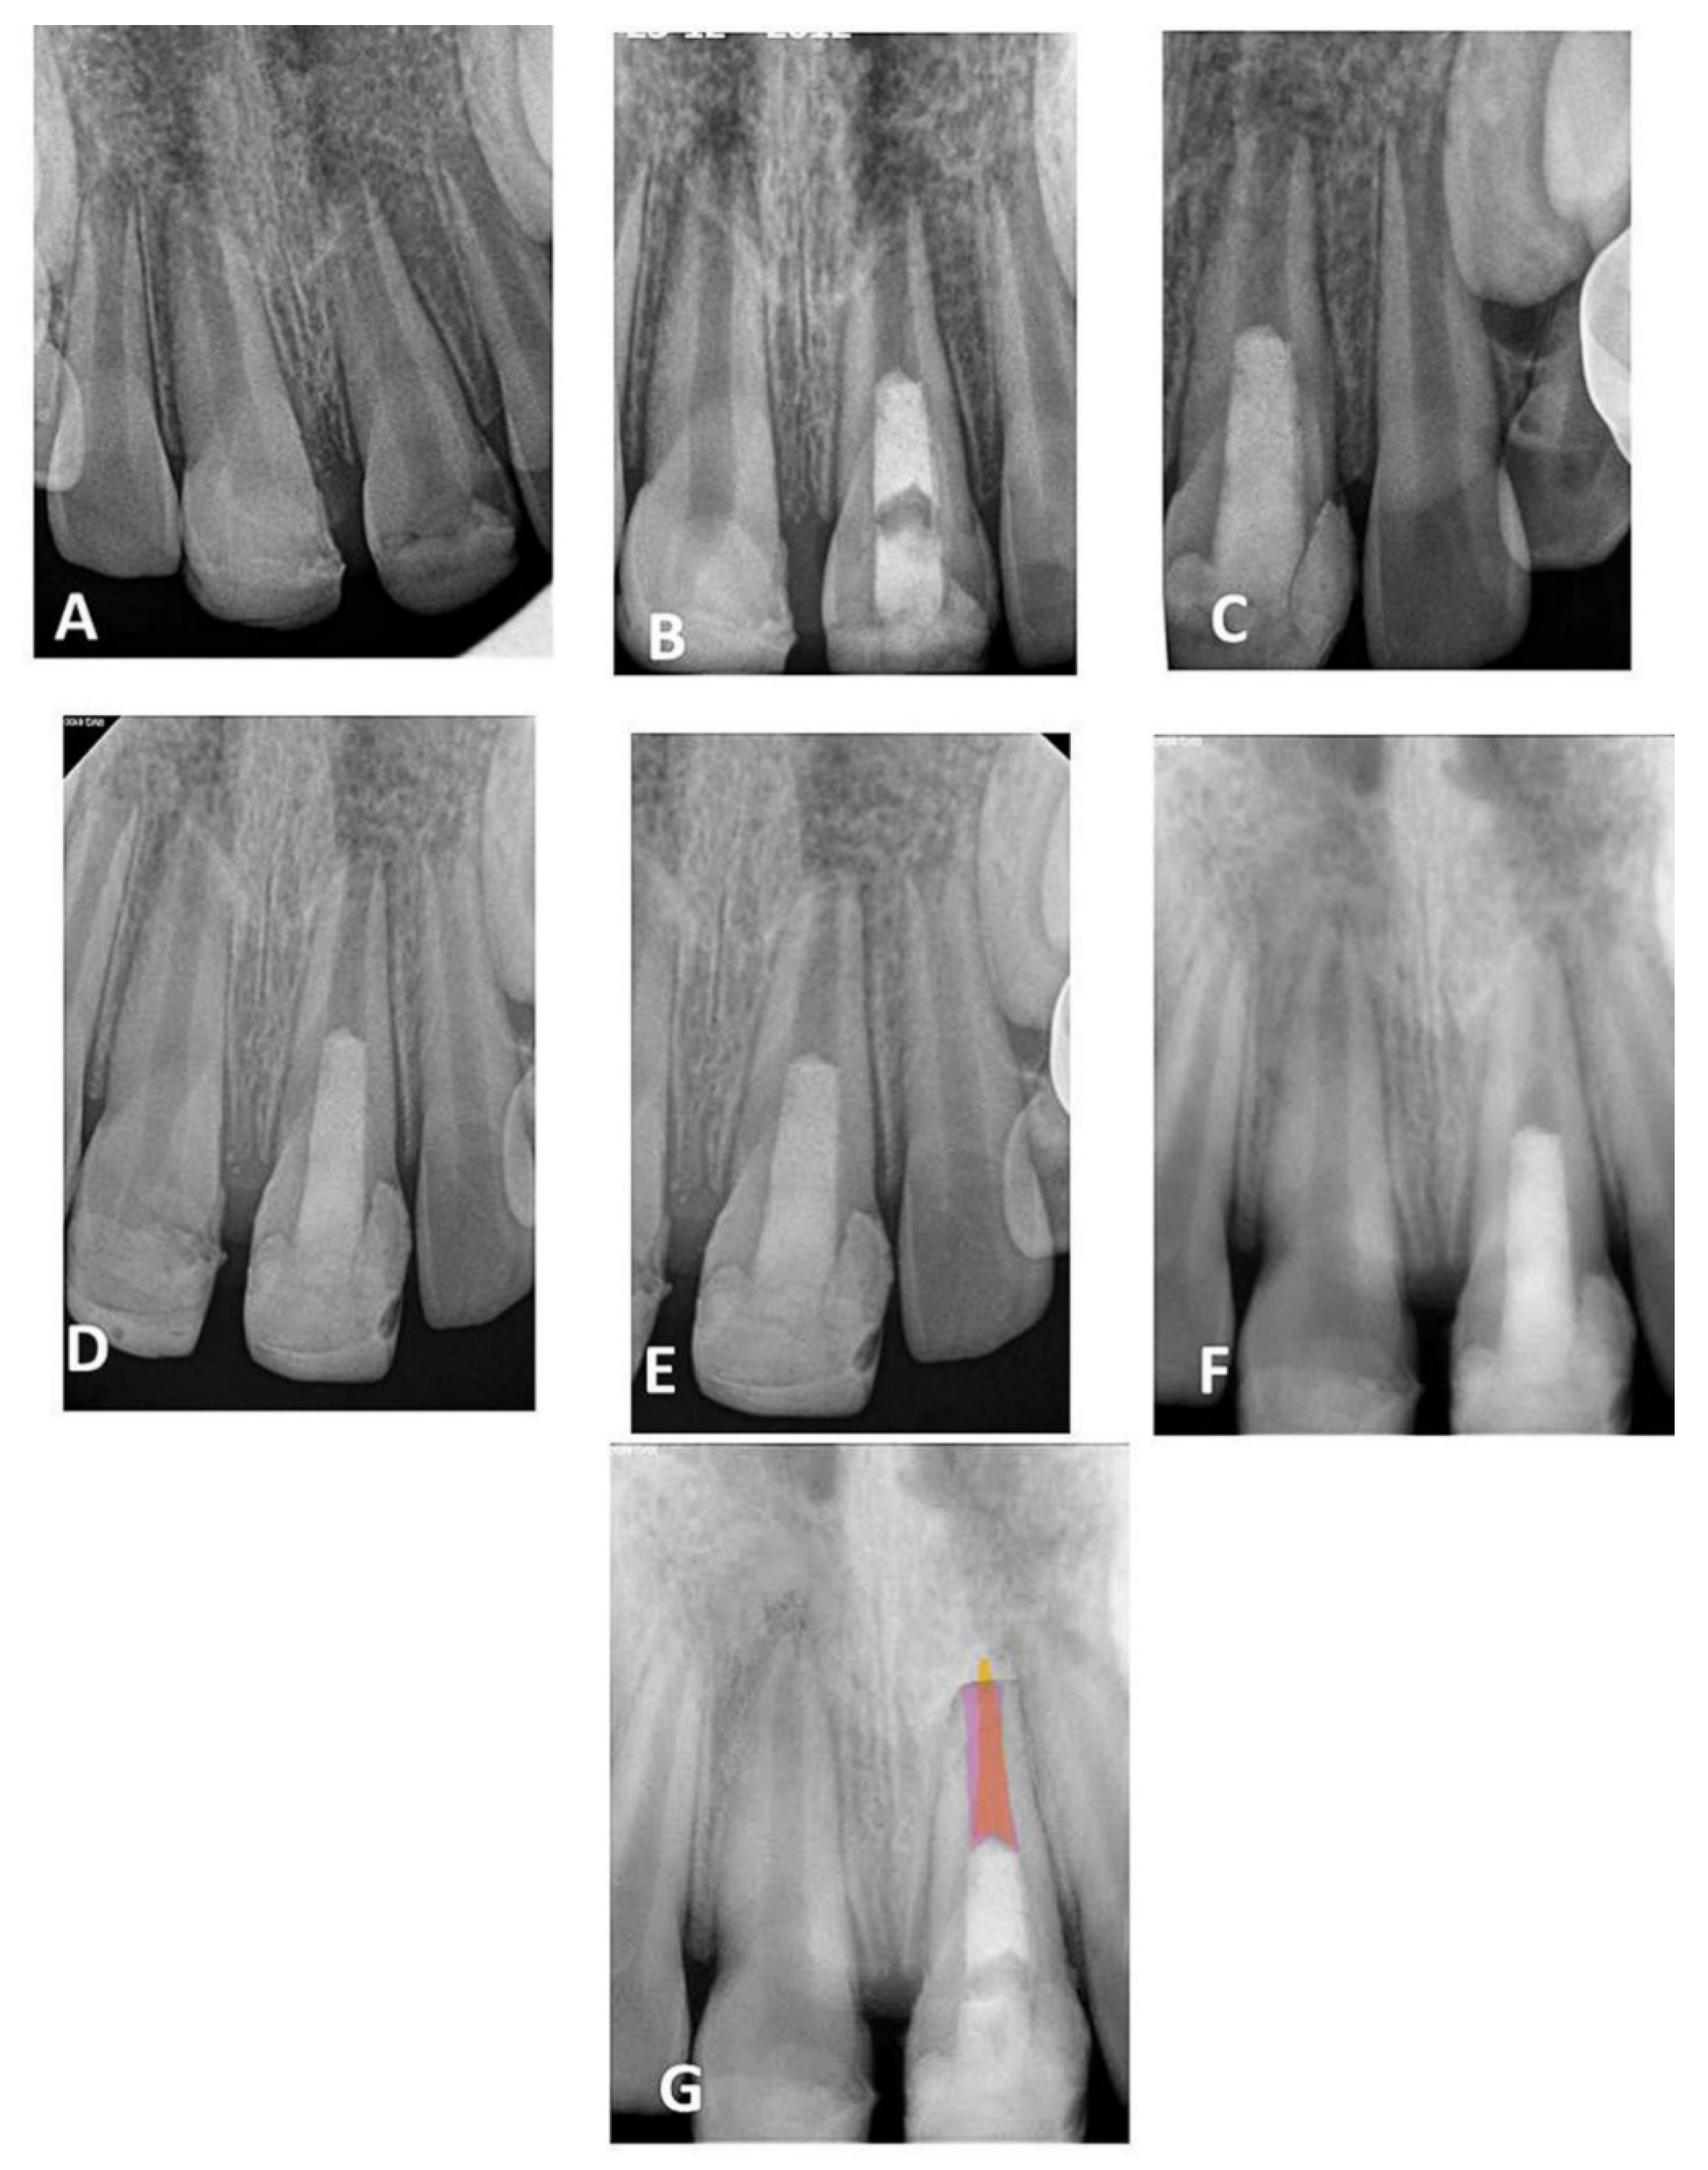

3. Results

3.1. Quantitative Assessment

3.2. Qualitative Assessment